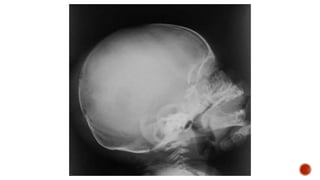

 AP and lateral radiographs of the skull show multiple tiny lucent areas with areas of

sclerosis in between, giving rise to salt and pepper skull appearance.

 Radiographs of both the legs, knees and left humerus show diffuse osteoporosis with

few well defined lytic areas.

 Radiograph of the hand shows osteoporosis with coarse trabeculations of the

phalanges with mild erosions along tteh radial aspect.

FINDINGS

 Osteopenia

 Subperiosteal resorption: classically along radial aspects of phalanges

 Floating tooth

 Subchondral resorption (lateral end of clavicles, pubic symphysis, sacroiliac joints)

 Subligamentous resorption(ischial tuberosity, trochanters)

 Brown tumors(more common in primary)

 Salt and pepper skull

 Rugger jersey spine

 Secondary and tertiary hyperparathyroidism may be associated with osteosclerosis of

renal osteodystrophy and osteomalacia of vitamin D deficiency

 Superior and inferior rib notching may be seen

SUBPERIOSTEAL RESORPT

SUBCHONDRAL

RESORPTION

SALT AND PEPPER SKULL